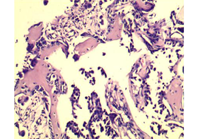

例1 患者女,65岁,因咳嗽咳痰、间断咯血11 d,于2012年12月26日就诊于我院。入院前,胸部CT检查示右上肺阴影,肿瘤性病变可能性大,左下肺感染性病变。PET-CT检查示,右上肺尖端软组织肿块影,伴代谢活性增高,考虑周围性肺癌。入院后,电子支气管镜检查示,双侧支气管黏膜炎症样改变。2013年1月14日行胸腔镜下右上肺叶切除术,术后病理结果示,右上肺腺癌中分化型。术后共行4个周期化疗,为培美曲赛联合奈达铂,末次化疗时间为2013年4月18日。2013年5月16日,开始行肺部病灶术后放疗,每次2 Gy,每周5次,共给予50 Gy。2014年7月,患者出现右手中度肿胀,局部皮肤发红,皮温升高,第二掌骨压痛,屈伸活动受限等症状。放射性核素骨扫描(ECT)检查提示,右手背骨质代谢活跃,性质待查,建议定期复查。2014年7月2日,行右手X线检查示,左手第二掌骨远端呈溶骨性破坏,余未见明显异常。2014年7月3日,右腕关节CT平扫结果示,右手第二掌骨见软组织肿块,骨质破坏,考虑转移(图1);余腕关节诸骨未见明显异常,关节间隙未见异常。手部病灶行穿刺活检,病理结果提示,右手掌骨转移性腺癌(图2)。2014年7月17日,开始对手部骨转移部位行放疗,每次5 Gy,每周5次,共给予50 Gy,同时使用破骨细胞抑制剂治疗。此患者后续在我院继续行放化疗等综合治疗,病情稳定,其总生存时间超过42个月,目前仍在随访中。